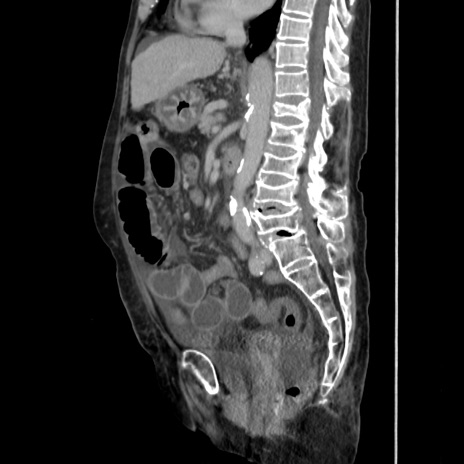

症例31(矢状断像)

【症例】80歳代 女性

【主訴】腹部膨満感

【現病歴】他院にて肝硬変にてフォロー中。1週間前から便秘、腹部膨満感、臍部腫瘤あり受診となる。

【既往歴】肝硬変

【身体所見】腹部膨隆あり、皮膚変化なし、疼痛なし。

【データ】WBC 4600、CRP 0.25